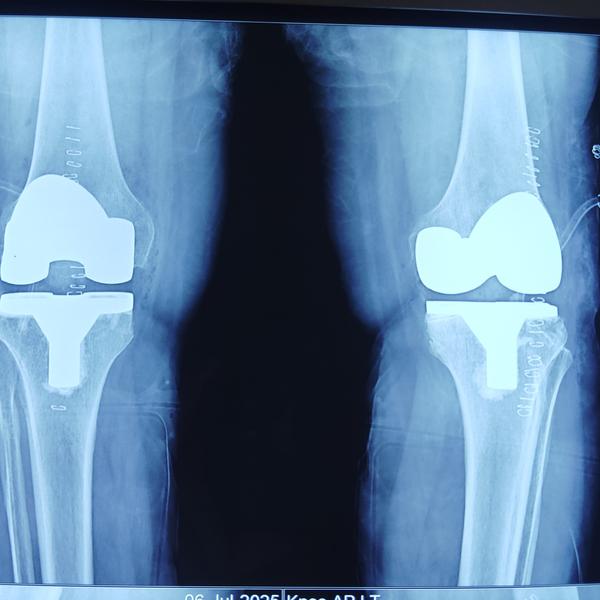

Successful KNEE REPLACEMENT surgery in Greater Noida

Best kee replacement dr in Greater Noida

knee replacement in greater Noida